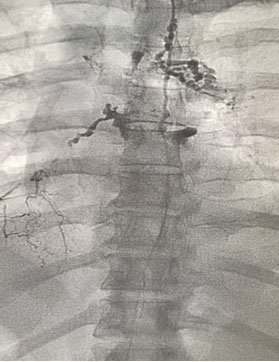

Embolization of leak (different patient) using coils